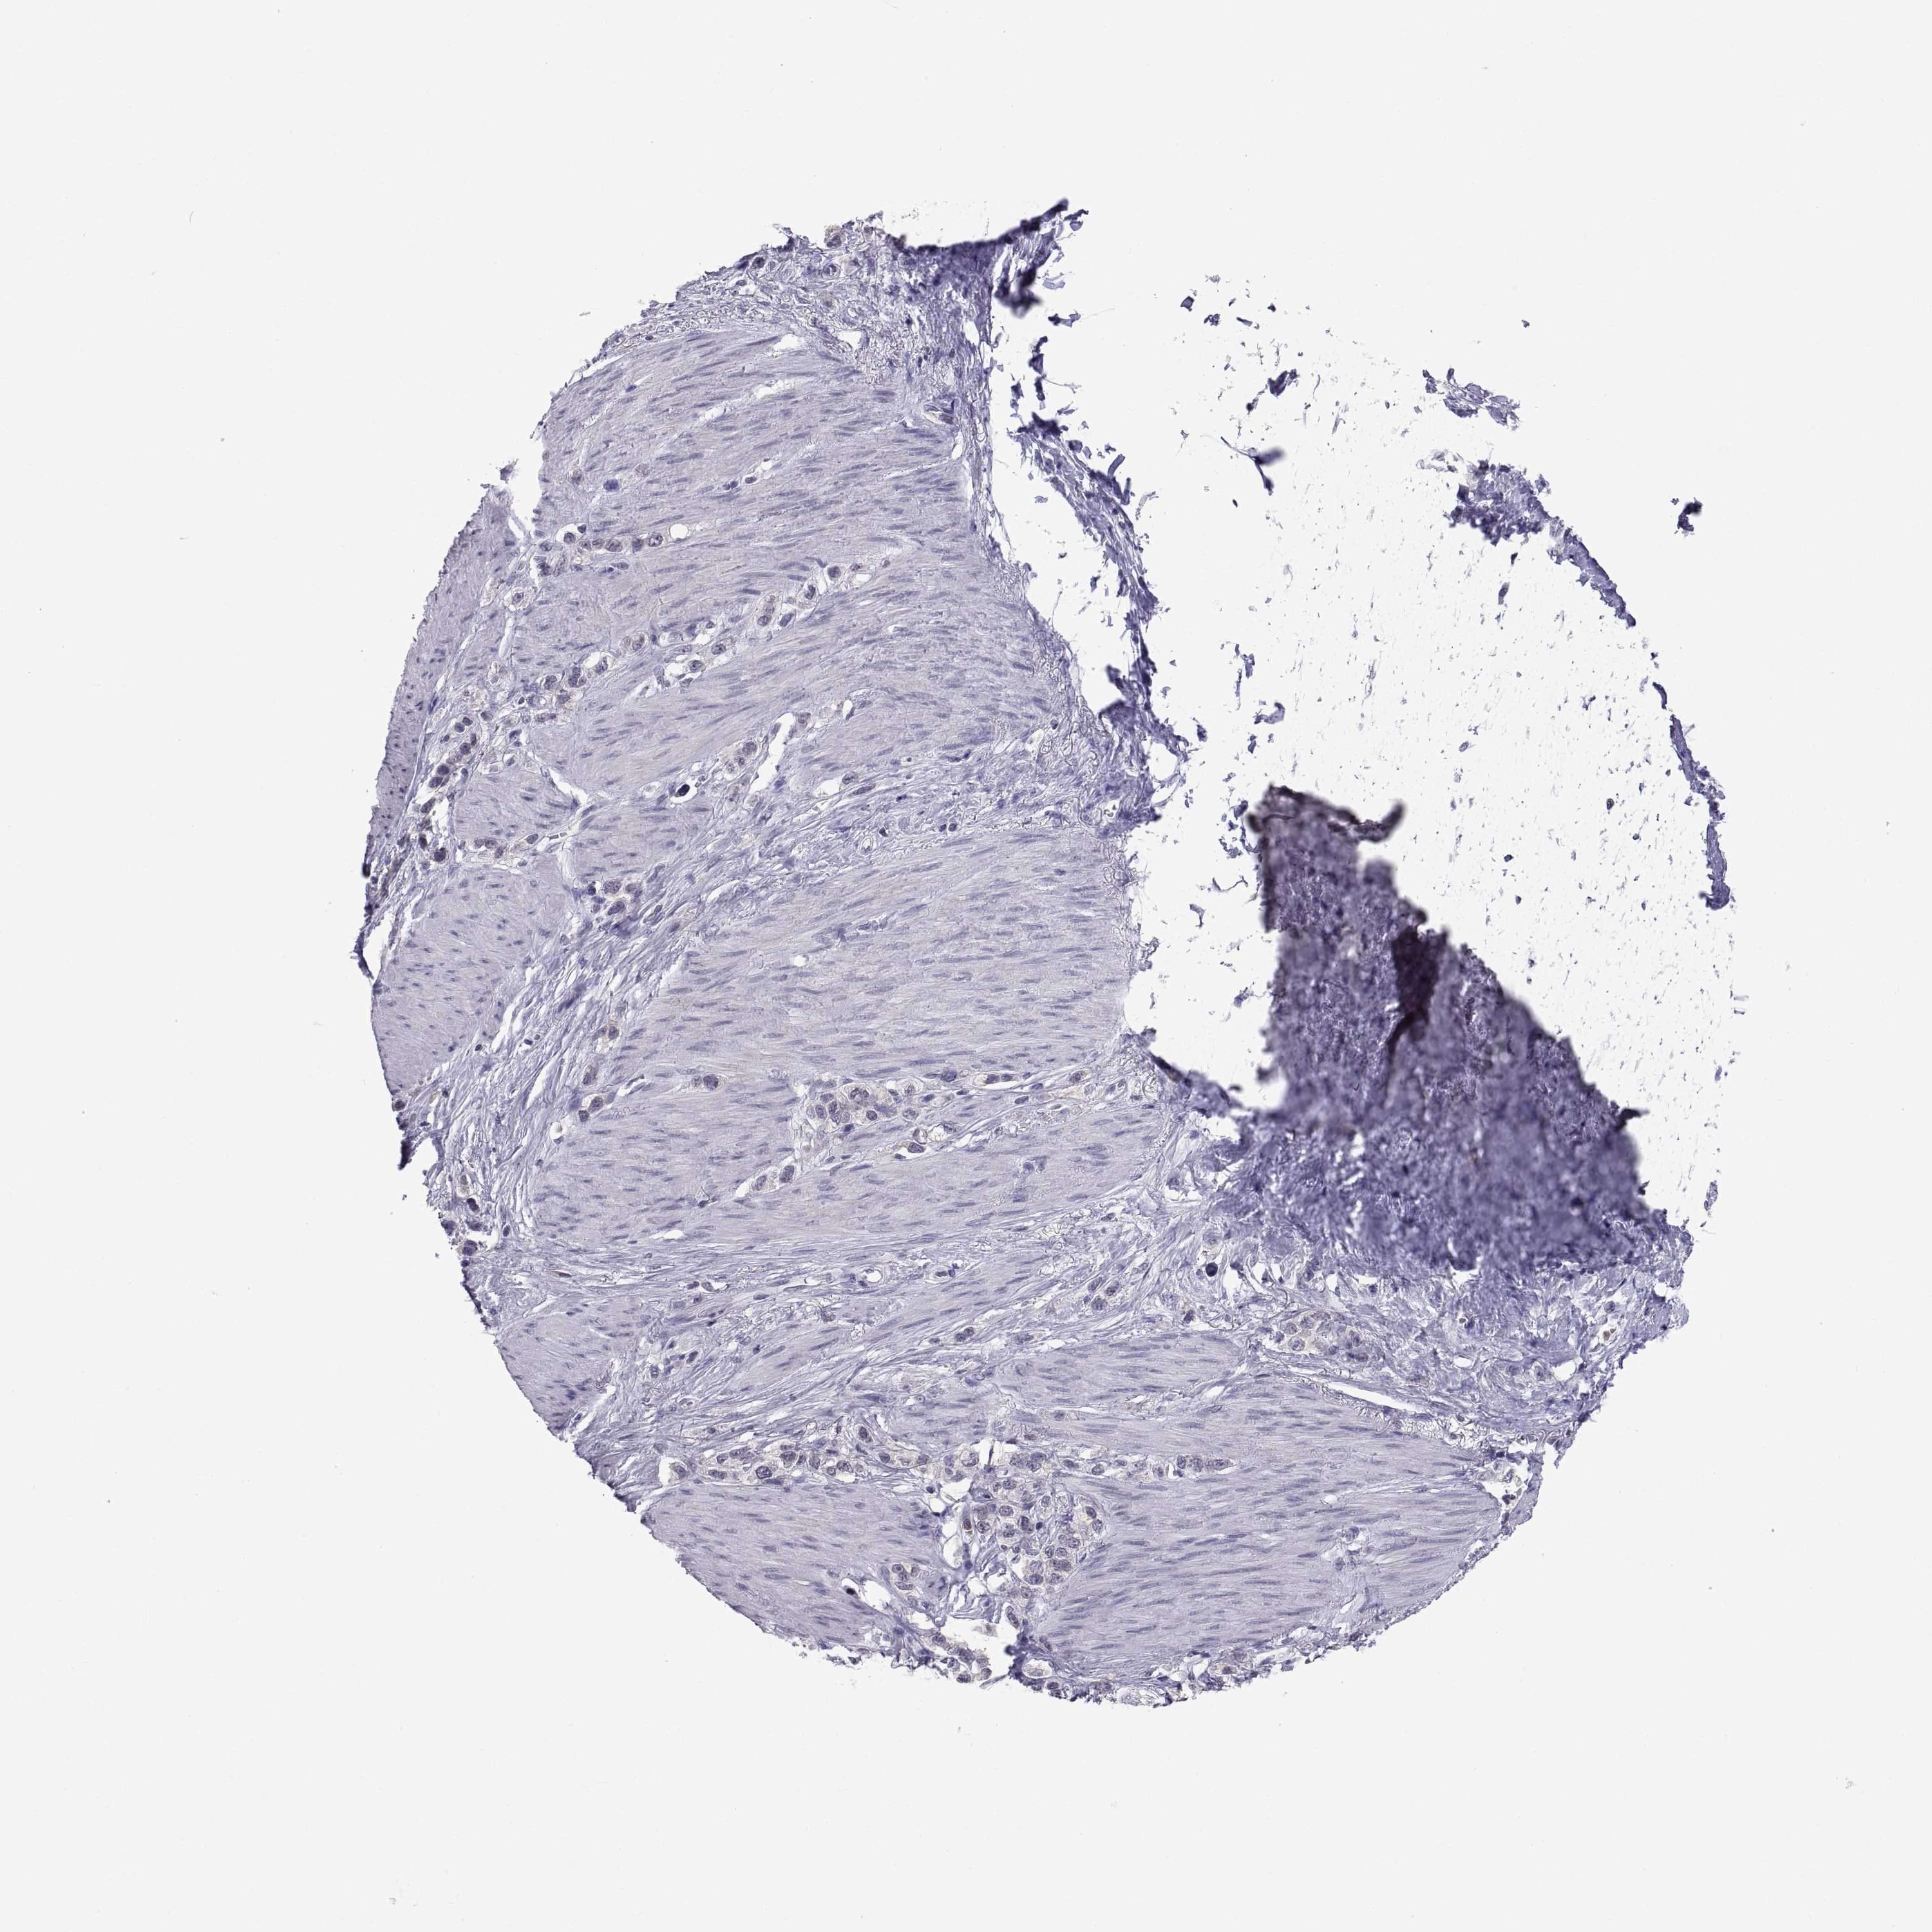

STOMACH CANCER - Protein expressioni

A mouse-over function shows sample information and annotation data. Click on an image to view it in a full screen mode. Samples can be filtered based on level of antibody staining by selecting one or several of the following categories: high, medium, low and not detected. The assay and annotation is described here.

Note that samples used for immunohistochemistry by the Human Protein Atlas do not correspond to samples in the TCGA dataset.

Antibody stainingi

Antibody staining in the annotated cell types in the current human tissue is reported as not detected, low, medium, or high, based on conventional immunohistochemistry profiling in selected tissues. This score is based on the combination of the staining intensity and fraction of stained cells.

Each image is clickable and will lead to virtual microscopy that enables deeper exploration of all samples and also displays staining intensity scores, fraction scores and subcellular localization as well as patient and tissue information for each sample.

Antibody HPA027221

Antibody CAB033130

Staining

High

Medium

Low

Not detected

Intensity

Strong

Moderate

Weak

Negative

Quantity

>75%

75%-25%

<25%

None

Location

Nuclear

Cytoplasmic/membranous

Cytoplasmic/membranous,nuclear

Adenocarcinoma, NOS

Adenocarcinoma, High grade